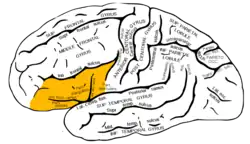

Hemisferio cerebral izquierdo: localización del giro frontal inferior. | ||

El giro frontal inferior es una circunvolución del cerebro. Está limitado por arriba por el surco frontal inferior, por detrás, por el surco precentral; hacia abajo, por el borde inferior del hemisferio cerebral y la cisura de Silvio. Queda dividido por las ramas anterior y ascendente de la cisura de Silvio en tres porciones: orbitaria, triangular y opercular.[1]